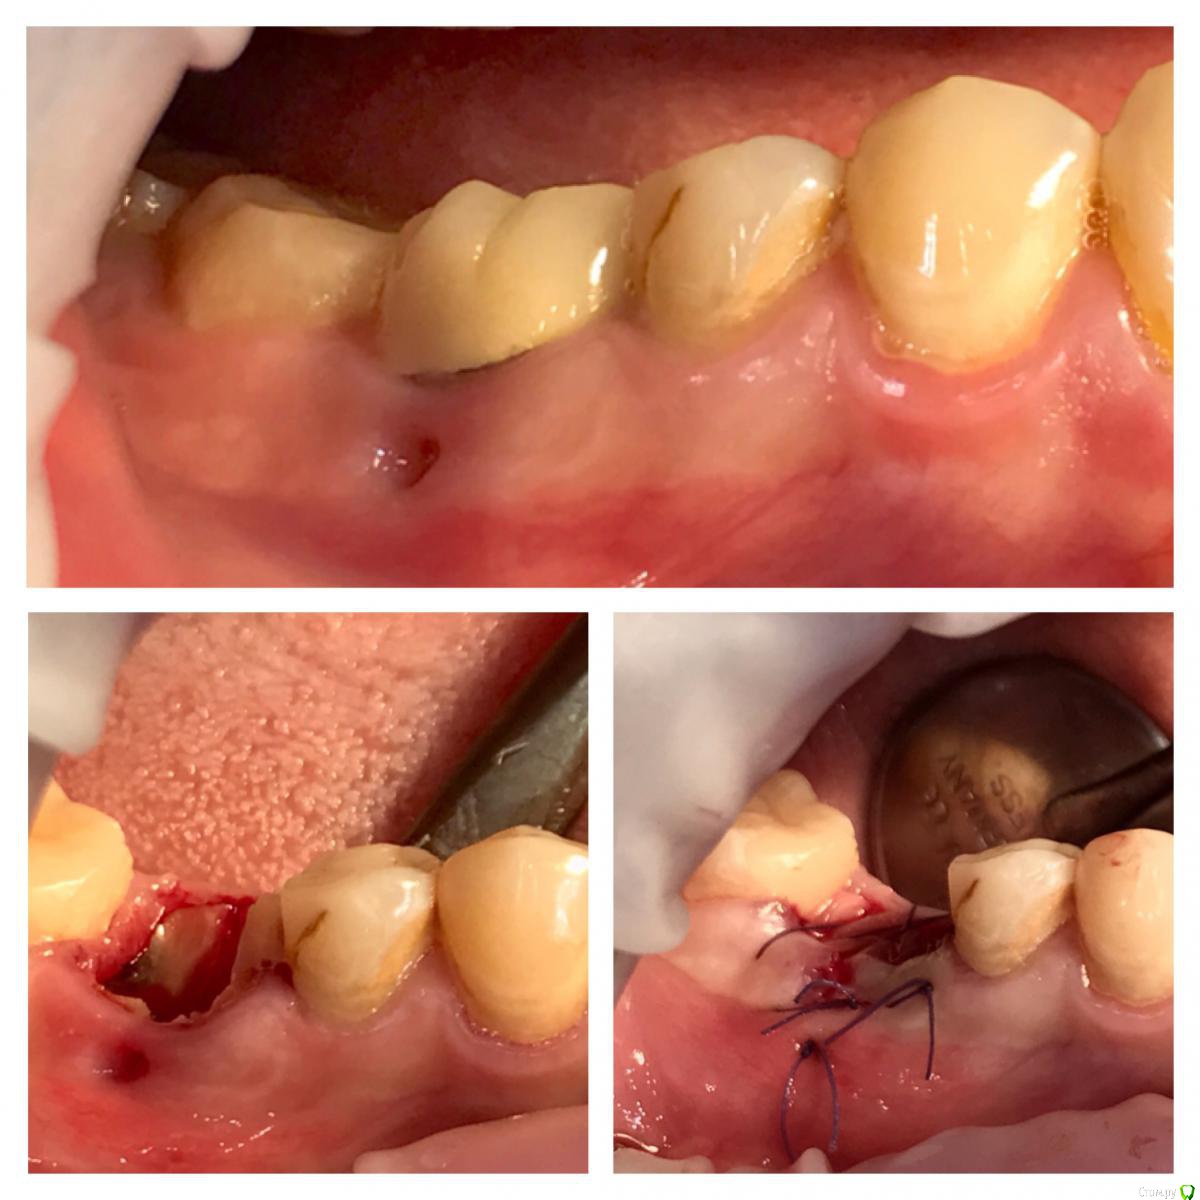

колесников Опубликовано 22 апреля, 2019 Поделиться Опубликовано 22 апреля, 2019 (изменено) И снова профайл спасает жизнь (облегчает жизнь имплантолога)Стандартная ситуация:36 периодонтит в стадии обострения с грануляциями,эксудацией,резорбцией компактной пластинки,дефицитом прикреплённой слизистой вестибулярного. Одна хирургия. Ноябрь 2018. Удаление,кюретаж,имплант Astra tech profile 4.5x9 под заглушку,торк около нуля. Вестибулярного сст,консервация графтом Sureoss 0,5 чипс с APRF,закрытие шайбой по Ноймайеру. Через неделю шайба несостоятельна-удалена. Пациентка созрела на удаление 37го. Выполнена декоронация в связи с отъездом пациентки,далее через 2 недели удаление и имплантация 37го. Промежуточный осмотр в январе. В марте установлены формирователи . Апрель контрольный осмотр. Периотест -5. Направлена на протезирование. Изменено 22 апреля, 2019 пользователем колесников 4 Ссылка на комментарий

колесников Опубликовано 23 апреля, 2019 Автор Поделиться Опубликовано 23 апреля, 2019 Разница от платформы до зенита 3 мм.Ещё раз. Вестибулярно дефект 9мм. Полное отсутсвие прикреплённой слизистой,язычное поднутрение и воспалительный процесс. Чтобы провести олномоментную имплантацию пришлось бы взять короткий имплант,заглубить его на 8мм от зенита,засыпать графтом,перекрыть мембраной,натянуть щеку и ждать-молиться чтобы края не разошлись и все не стухло. А после 2 -3 десневые пластики и глубокая шахта. Господа! Коллеги! Где сроки? Где бюджет? Где прогнозы? Ладно имплант и его глубина, это не так существенно,я вам показал как из ничего за 1 визит получить кератинизированую и прикрепленную слизистую без основания Ссылка на комментарий

колесников Опубликовано 24 апреля, 2019 Автор Поделиться Опубликовано 24 апреля, 2019 Для чего нужно асл при одномоментной имплантации с бешенным дефицитом десны? Чем "теория десневых каркасов" отличается от классической методики костной регенерации кроме отсутсвия коллагеновой мембраны в целях экономии?Как можно считать одномоментную имплантацию с нкр в инфицированной лунке в стадии обострения прогнозированным методом лечения?С уважением и благодарностью за то, что делитесь опытом и мнением!1)Асл конечно же 2ым этапом,после формирования аугментата2)классическая методика костной регенерации,точнее получений аугментата-это всеголишь одна из возможных составляющих будущего десневого каркаса. Вестибулярно маргинальная десна располагается на богатой коллагеном десневом валике,а тот в свою очередь на костном гребне (нативном или аугментате), который в свою очередь питается от этого валика. Классическая нкр методика делает упор на объём кости,оставляя меньший объём десне. Есть чисто десневой каркас по гамборене. Но в этом варианте есть ограничения по вертикали. Мое предложение-дополнительные каркасные валики (зацепы) для поверхностной десны. В частности скос у профайла это дополнительный уступ для прикреплённой слизистой. Можно дополнительноиспользовать супрастуктуры а качестве поддержки. Мне удавалось делать каркас высотой до 10мм без костной поддержки. После стимуляции этого десневого каркаса,кость прибавляет в объёме 3) одномоментная имплантация всегда более прогнозируемая чем отсроченная. Питание по разному осуществляется и регенерация иначе происходит. Стерильной раны в полости рта не существует в принципе,отсрочено или одномоментно вы заходите. Прикорневая инфекция ограничена усиленной капиллярной сеткой,что благотворно сказывается на регенерации,наша задача :санация лунки и контроль вторичного инфицирования 2 Ссылка на комментарий